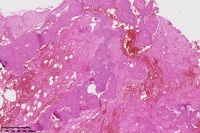

右胫骨内组织,单纯性骨囊肿?

性别

男

年龄

12岁

临床诊断

内生性软骨瘤?骨囊肿?

标本名称

右胫骨内组织

图1